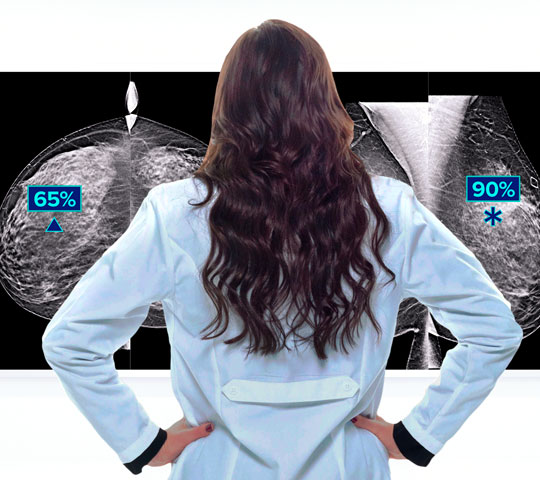

Hologic is transforming breast care. We apply cutting-edge science to accelerate discovery, improve efficiency and continually sharpen precision.

Time is precious when it comes to effective detection, diagnosis and treatment of breast cancer. We strive to save you time at every step along the Continuum of Care.